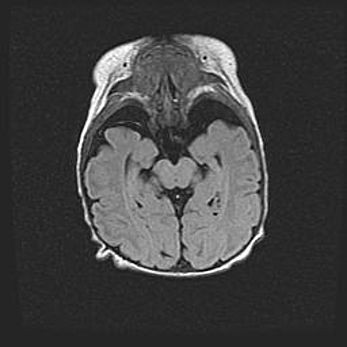

Подострая гематома правой гемисферы мозжечка.

Наружная гидроцефалия.

Возраст: 15 дней

Вес: 3100 г

Пол: женский

Окружность головы: 37 см

Срок гестации: 35-36 недель

При открытой наружной форме гидроцефалии у новорожденных расширяются и переполняются субарахноидные пространства.

Кровоизлияния в мозжечок имеют две клинико-анатомические формы: полушарные гематомы и кровоизлияния в червь.

К появлению этой патологии может привести: повреждения головного мозга, возникающие в результате асфиксии и гипоксии плода при беременности, или травмы во время родов. Редко гематома мозжечка может быть результатом первичной коагулопатии и сосудистой мальформации, диссеминированном внутрисосудистом свертывании, изоиммунной тромбоцитопении.